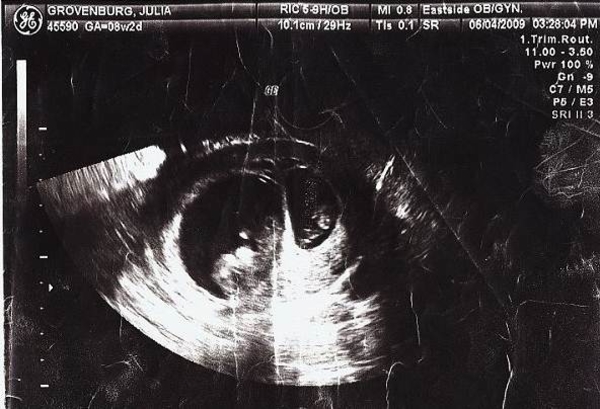

Когда врачи увидели на ультразвуке двух детей на разных стадиях развития они были обескуражены и сообщили супругам, что они ожидают двоих детей, но это не близнецы.